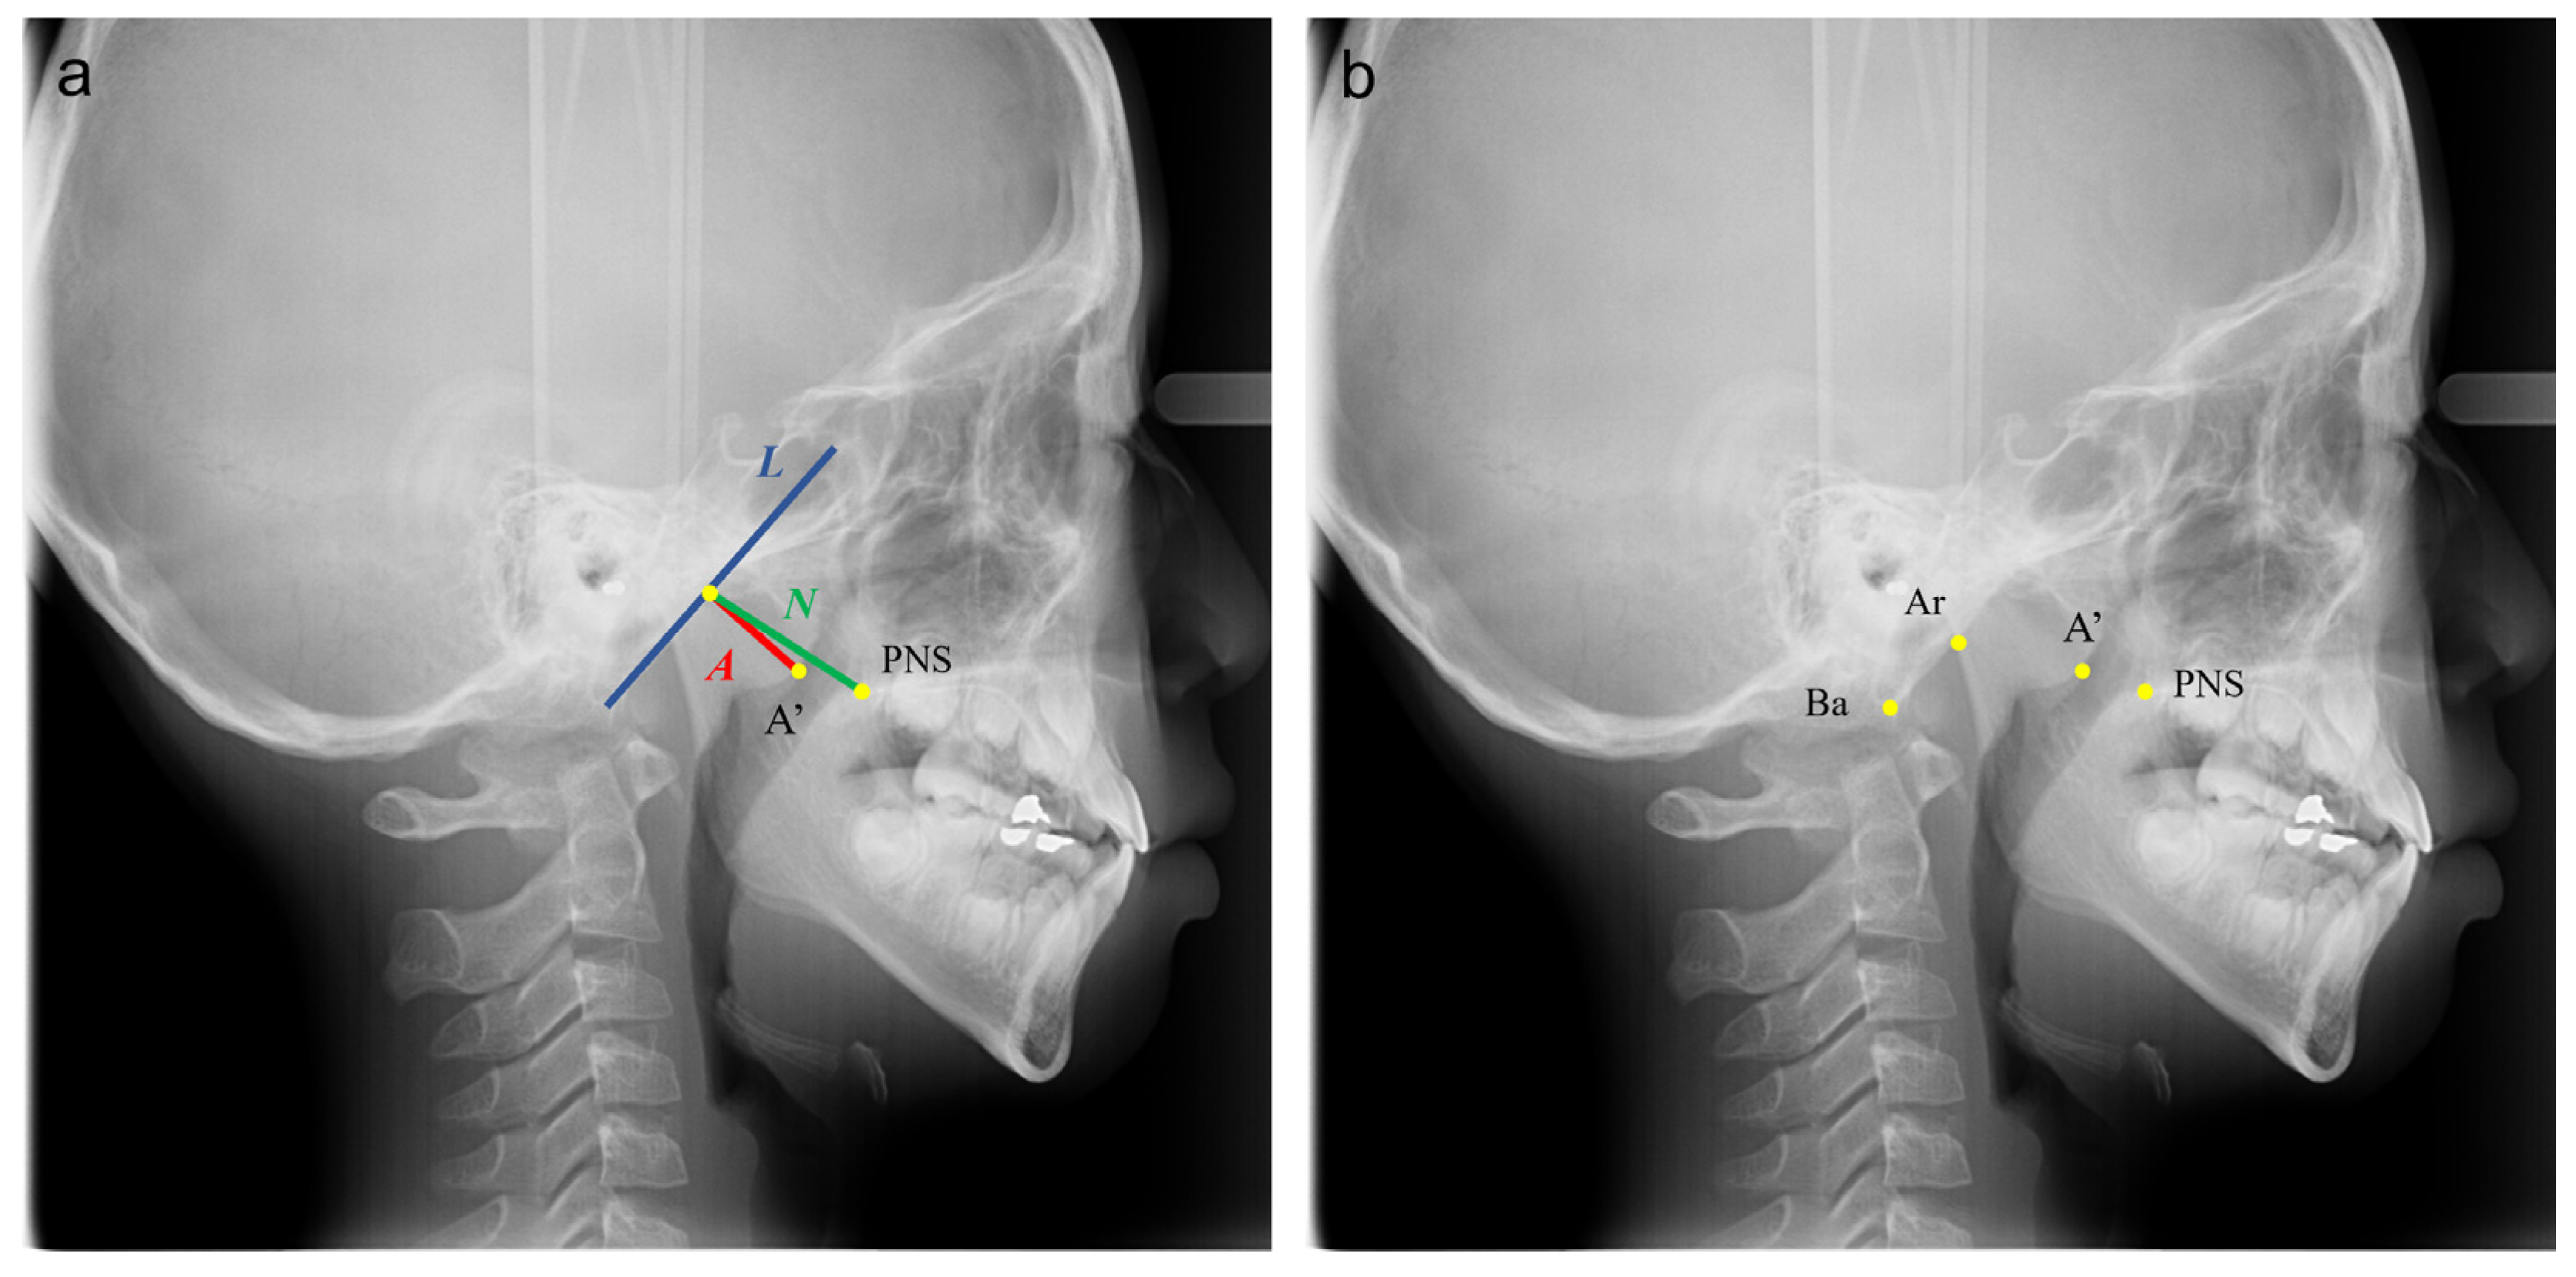

2.1. Samples and Identification of Landmarks